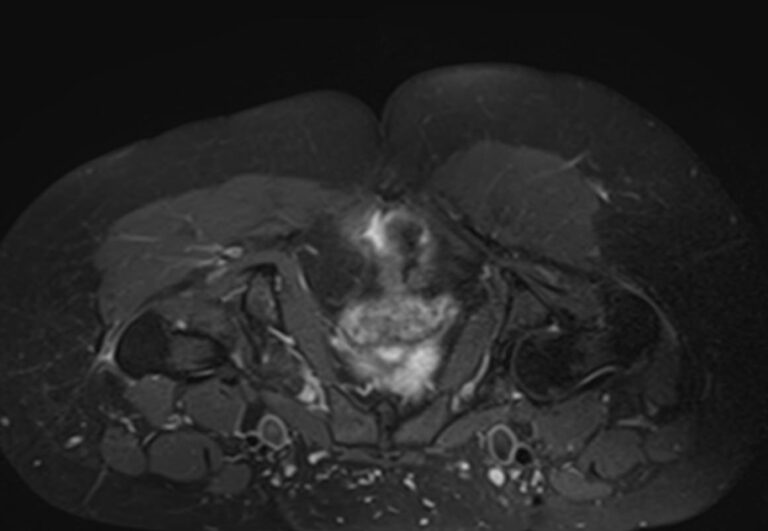

Чаще всего ягодичная область подвержена развитию воспалительных заболеваний, травматических повреждений и опухолевых процессов. Наиболее эффективным способом диагностики патологии мягких тканей ягодичной области является магнитно-резонансная томография. При применении данного метода не используется вредное ионизирующее излучение, как при обычном рентгене или КТ, при этом МРТ дает наибольшую информацию о состоянии мягкотканных структур, выявляя патологические очаги размером от 1 мм.

МРТ данной анатомической области выполняется в большинстве случаев в стандартном режиме без применения контрастного усиления. Однако при подозрении на развитие опухоли необходимо введение контрастного препарата. Для этого используется контрастное вещество, созданное на основе гадолиния (металл, обладающий особыми свойствами в зоне действия магнитного поля). Контраст избирательно накапливается в очагах поражения и обусловливает их яркое свечение под влиянием магнитного поля томографа. Это позволяет, в частности, выявлять опухоли на ранних стадиях развития и дает исчерпывающую информацию о структуре опухолевого образования, его границах, степени кровоснабжения и распространения на близлежащие органы и ткани.

При проведении МРТ можно выявить следующие заболевания ягодичной области:

- Воспалительные заболевания ягодичной области вследствие травм, нагноения гематом, после проведения инъекций (абсцессы, флегмоны ягодичной области).

- Доброкачественные и злокачественные опухоли, которые располагаются в мягких тканях ягодичной области.